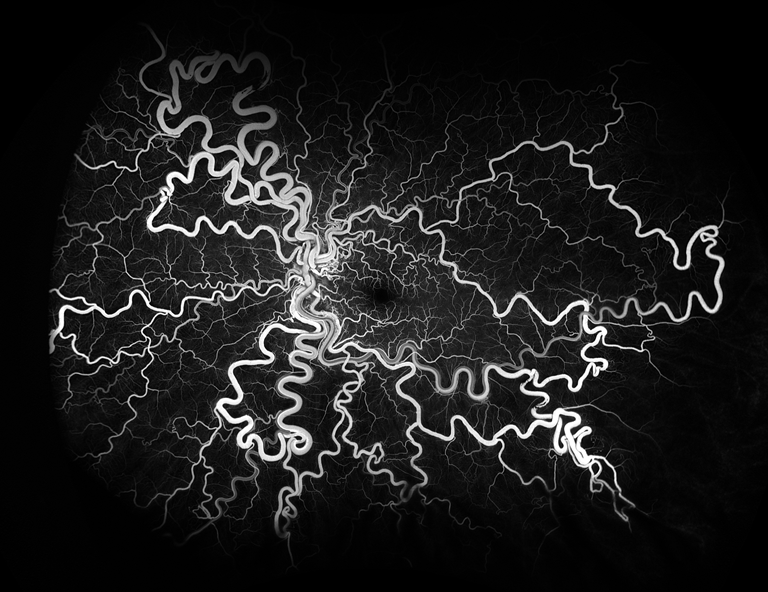

Wyburn-Mason Syndrome

Presented by Stephanie Burke, MS, CRA, OCT-CThis photograph won Best of Show for the 2024 ASCRS/OPS Exhibit and 1st Place in the category "Retinal Fluorescein Angiography".